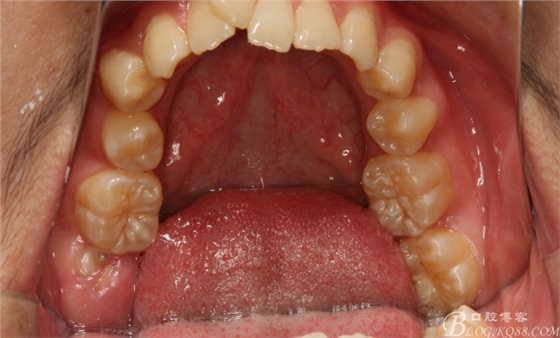

圖1.術(shù)前閉口位影像:深覆合。

圖4.上腭部影像:腭側(cè)粘膜圓形隆起